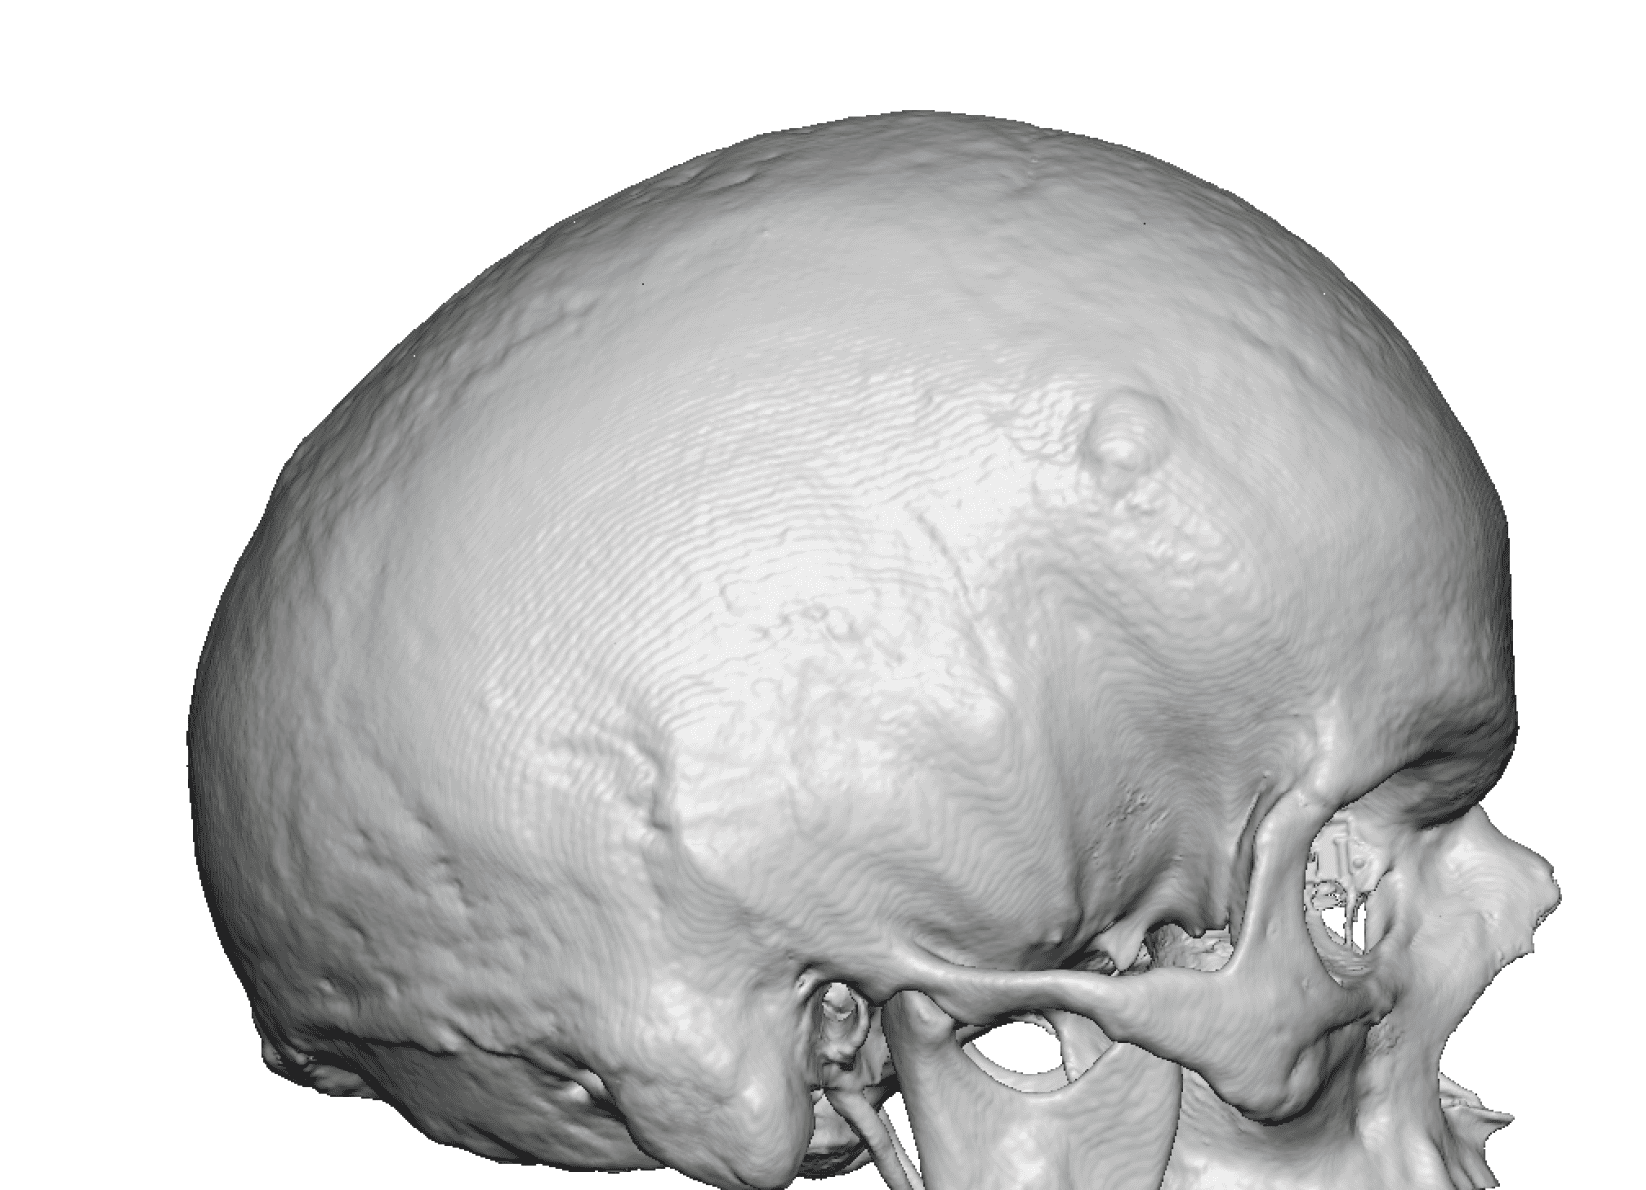

Desire for change of head shape from front view form an inverted V shape to a rounder and wider head shape.

Placement of custom extended forehead-temporal implants through incisions in the crease behind the ear. (he had a prior back of head skull implant which is green in the implant designs and which the head widening implants partially covered it)

Desire for change of head shape from front view form an inverted V shape to a rounder and wider head shape.

Placement of custom extended forehead-temporal implants through incisions in the crease behind the ear. (he had a prior back of head skull implant which is green in the implant designs and which the head widening implants partially covered it)